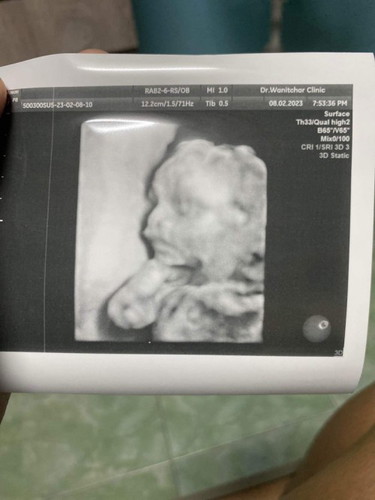

ขอสอบถามความเห็นแม่ๆหน่อยค่ะ ตั้งครรภ์ 20w2d ไปซาวด์มาคุณหมอบอกลูกปกติดี แต่ทำไมเราเห็นรอยแปลกๆตรงปาก หรือเราคิดไปเองคะ

ถ้าหมอไม่แจ้งปากแหว่งเพดานโหว่ ก็ปกตินะคะ เพราะตอนเราซาวด์ภาพบางส่วนก็แปลก ๆ ภาพช่วงกระหม่อมขาดไป หมอแจ้งว่าอันนี้ไม่ใช่หัวไม่ปิดนะ แต่ภาพอาจจะแสงส่องไม่ถึง จะเห็นชัดกว่านี้ตอนอายุครรภ์มากขึ้นด้วยค่ะ ตอนนี้เนื้อหนังยังไม่มาก

แม่อาจจะคิดมากไปค่ะ อาจจะเป็นน้ำคร่ำเครื่องอัลตร้าซาวด์ไม่ชัดค่ะ

เท่าที่ดูน้องปกตินะคะ เป็นรอยๆรูจมูก รออาบุครรภ์เพิ่มขึ้นก่อนก็ได้ค่ะ